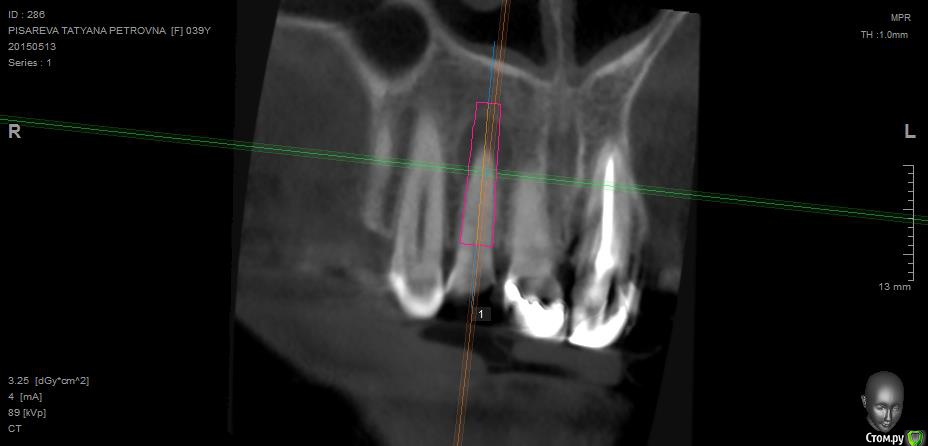

Evikrol Опубликовано 13 мая, 2015 Автор Поделиться Опубликовано 13 мая, 2015 Можно ли в таком случае одномоментно удалить и поставить? 18 мм если заякорится то и временную. Ссылка на комментарий

diesel87 Опубликовано 13 мая, 2015 Поделиться Опубликовано 13 мая, 2015 Можно, если выскрести все, а лучше на апексе целиком вытащить. И про промыть чем нибудь ядренным я где то читал еще. Ссылка на комментарий

Аслан Опубликовано 14 мая, 2015 Поделиться Опубликовано 14 мая, 2015 Я бы не стал ставить винт сразу.Во-первых его надо сместить апикальнее на 3 мм, какараз упрется в кортикалку, Во-вторых. Я бы вышкреб с засыпал под мембрану и стт, но края не сводить, а уж потом винт и коронка сразу. 1 Ссылка на комментарий

Evikrol Опубликовано 14 мая, 2015 Автор Поделиться Опубликовано 14 мая, 2015 (изменено) Аслан и через сколько месяцев крутить в таком случае? Если не биоос а ауто взять, три? Изменено 14 мая, 2015 пользователем Evikrol Ссылка на комментарий